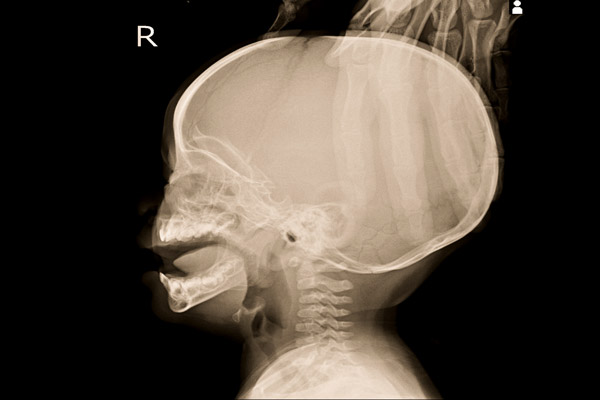

Genellikle yenidoğan bebeklerde görülen Gün Batımı Sendromu (Graefe), gün batımı hastalığının belirtileri ve nasıl bir tedaviyle karakterize edildiği merak edilen konular arasında yer alır. Tıpta, Semptom Graefe ya da batan güneşin hastalığı ya da Hidrosefali olarak adlandırılan hastalığın daha çok yenidoğan (0-2 ay) bebeklerde doğumsal olarak ortaya çıkar ve en büyük grubu bu yaş aralığının oluşturur. Hidrosefali hastalığının; fontanelin (bıngıldak) gergin olması, başın anormal gelişmesi gibi fark edilebilir belirtileri vardır. Bebeklerdeki günbatımı sendromunun diğer belirtileri arasında ise iştah azalması ve bebeğin göz bebeklerinin alt göz kapağının altına ilerlemesi (batan güneş manzarası - gözlerin yukarı doğru bakamaması) vardır. İşte bebeklerde gün batımı sendromu nedenleri ve detaylar...

Hidrosefali, en genel tanımıyla kafa içerisindeki suyun miktar olarak arttığı durumlar olarak açıklanmakla birlikte, ilk akla gelenin kafa büyümesi olduğu, daha çok yenidoğan (0-2 ay) bebeklerde doğumsal olarak ortaya çıktığı ve en büyük grubu bu yaş aralığının olduğu belirtilir.

Hidrosefali, mevcut hastaların büyük bir çoğunluğunda, beyin omurilik sıvısının dolaşım yolunda bulunan herhangi bir noktada meydana gelen tıkanmaya bağlı olarak oluşur. Söz konusu tıkanmanın beyinde bulunan karıncıkları birbirine bağlayan kanallarda ya da deliklerde olabildiği gibi emilimin olduğu son noktada da olabileceği belirtilir. Oluşan tıkanmanın nedeninin alınan kafa darbesi, geçirilen bir enfeksiyon veya tümör olabileceği ifade edilir. Hidrosefali doğuştan olabilir ya da sonradan gelişebilir. Sonradan gelişen hidrosefali gelişiminin üç nedeni olabileceği vurgulanır. Bu nedenler şöyle ifade edilir;